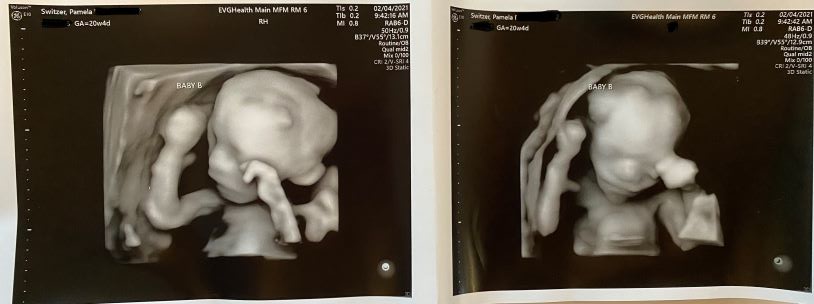

02/04/2021: 20w4d Twins Update | Dopplers improved, no surgery today

Life until March 13, 2021 (26 weeks) is now lived scan to scan.

Today, the scans showed babies with beating hearts and lots of movement. Their fluids remain similar and their MCA Dopplers improved. Joshua’s (Baby A) reduced to around 1.5x AVG and Daniel’s (Baby B) has returned to normal. Our MFM perinatology and fetal surgeon team has admitted that they are somewhat baffled at the array of symptoms the Switzer twins are displaying which do not identify with any known constellation of symptoms indicative of a specific complication. Time and development will further refine our diagnosis. Our babies are not safe until they are delivered – they begin to become viable at 26 weeks on March 13th. Dr. Walker has adjusted my target delivery date to no later than 32 weeks on April 24 if we are fortunate enough to make it that far.

While our babies have some characteristics of TAPs, they definitely have sIUGR with artery to artery anastomosis. Friday 2/15 we’ll see a pediatric cardiologist to find out if Joshua has a problem with his heart that will require surgery at birth, or perhaps he’s just behind in growth. It’s clear that these symptoms and stats can change in 24-48 hours, but aren’t likely (no guarantees, of course) to change dramatically in under a week until I’m farther along. So, we continue expectant management on a weekly frequency unless something dictates a change to more frequent 2-3 times per week monitoring (which has happened 3 out of the last 6 weeks). At 24 weeks gestation (by the week of Feb 22, 2021) or sooner I’m to be admitted to hospitalized bed rest to have daily monitoring and daily access to emergency surgery. Until then, all I can do is maintain side-lying horizontal rest to increase bloodflow to the uterus and placenta and 175g protein/2500 healthy calories per day to boost nutrition, all in an effort to get more nutrition to Joshua.